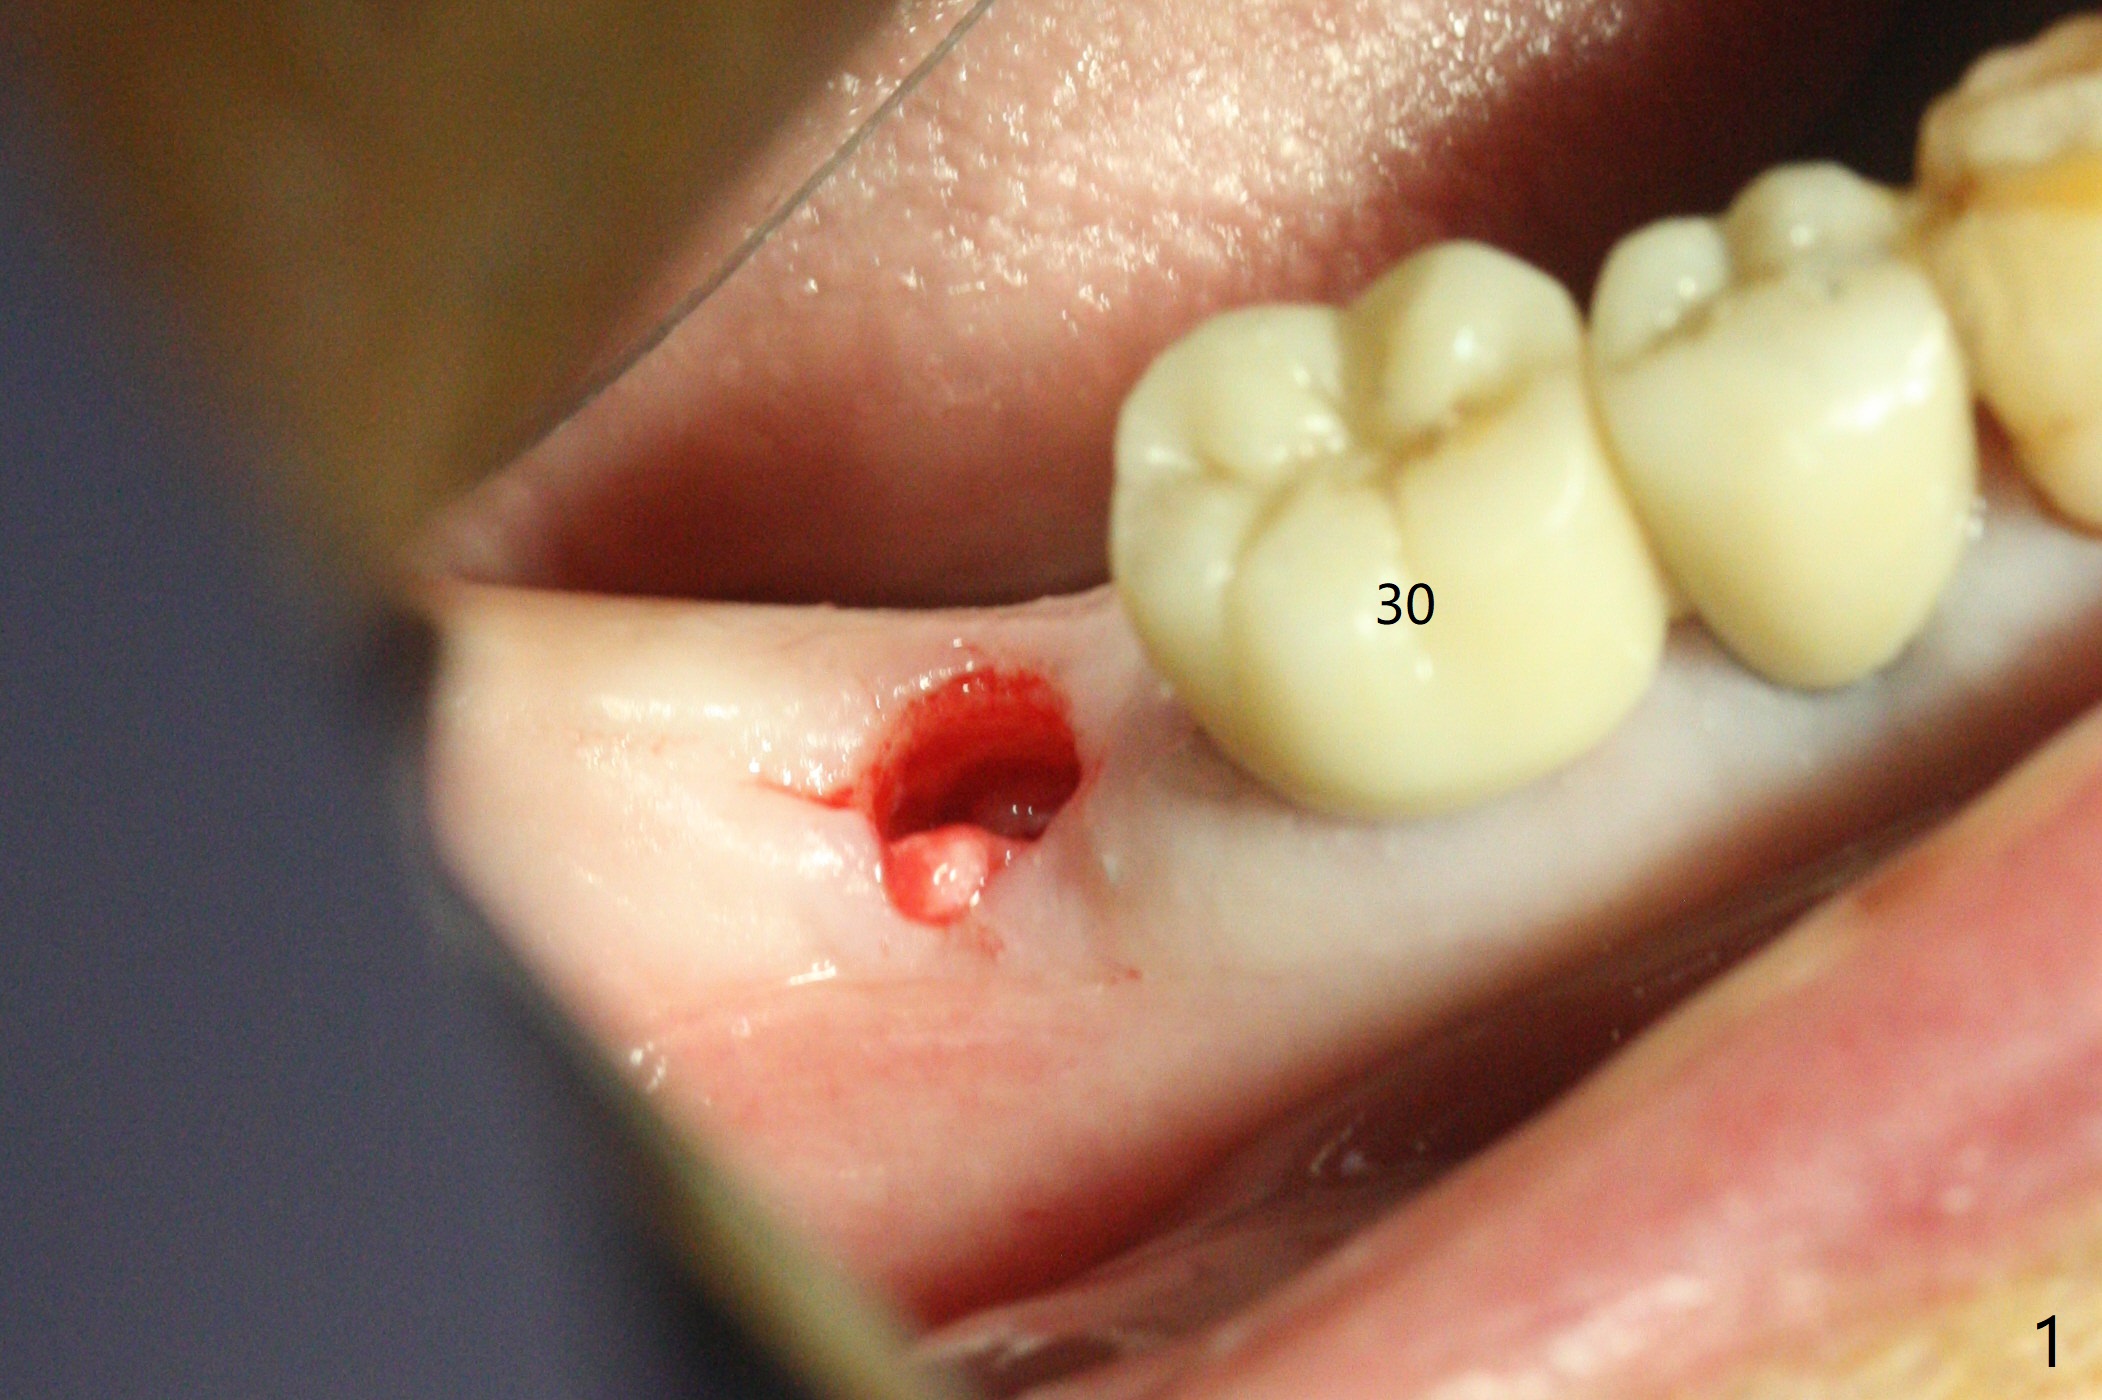

After 2.2x10 mm drill at #31 (Fig.1), bone expansion is conducted with 1.7/3.1 mm and 2.4/3.7 mm Expanders with guide (Fig.2) and 3.0/4.4 mm one without guide. Guided surgery resumes as planned to remove the lingual and apical bone. The buccal bone looks porous from the osteotomy opening. Mixture of autogenous and allograft is packed against the bone plate from the osteotomy before implant placement, but the 5x10 mm implant is unable to be seated completely. After removal of the bone graft from the osteotomy site and use of 4x11.5 mm drill for ~ 1 mm, the implant is seated with ~ 60 Ncm (Fig.3). With buccal incision, bone graft is placed over the distobuccal exposed implant thread (Fig.4 *) following placement of a 6x4 mm healing abutment. Oozing from the wound (thrombocytopenia) is controlled by Polysyn suture and perio glue (Fig.5). The mesial wound dehiscences 7 days postop when DO composite is placed at #28 (Fig.6). Two days later the patient returns because of hemorrhage in brushing. After placement of a taller healing abutment (6x7 mm) with triple antibiotic ointment (although the gingiva cuff is healthy), periodontal dressing is applied. Then the wound heals. The longer healing abutment remains seated (Fig.7 <) without interference from the crest (*) 4.5 months postop. A smaller cemented abutment (5.2x4(4) mm) is chosen with the same outcomes (well seated without gap (Fig.8 < between the implant and abutment), clearance from the crest (*)) 5 months postop. The final crown is cemented 6 months postop with distal access hole (Fig.9 black line), which may be related to design using normal 2nd molar tooth. In fact this patient has small teeth.